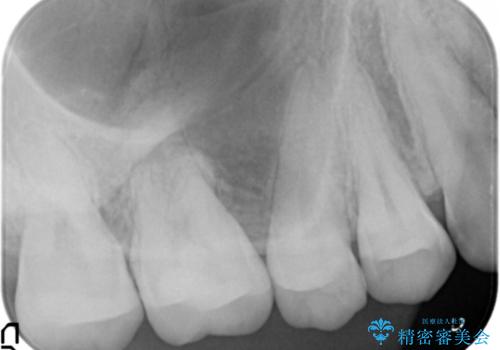

精査したところ、奥歯に充填された保険内のコンポジットレジンの適合が悪いことにより、汚れがたまりやすい状態でした。

不適合なレジンを除去し、セラミックインレーによる治療を行いました。(右上76左上67右下7の計5本)